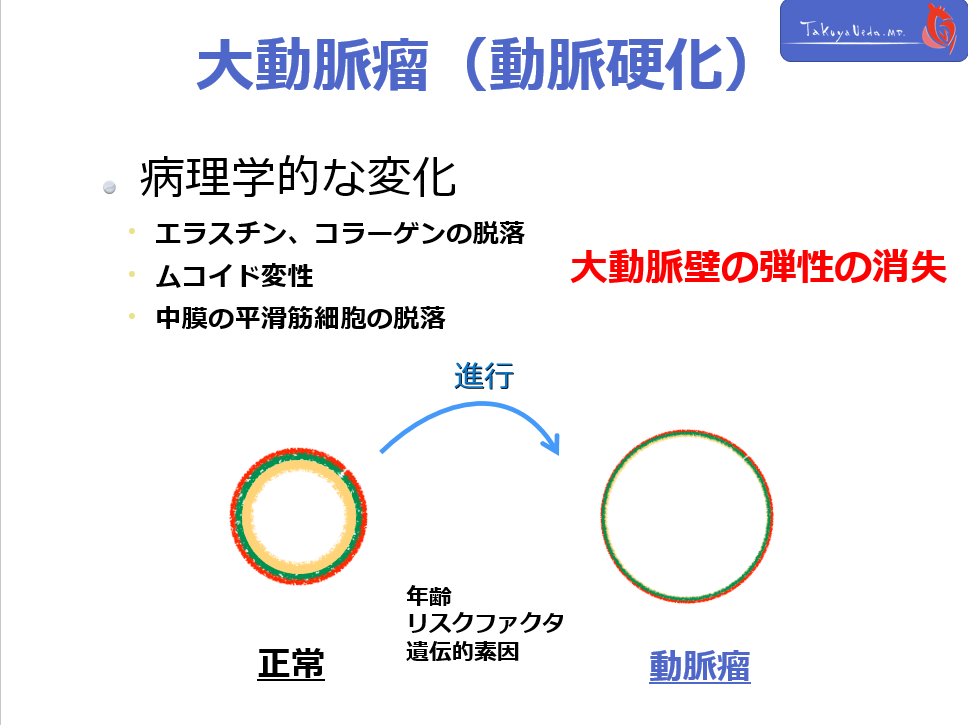

各病態の疾患概念を考える際に、大動脈の壁構造を理解することは非常に重要です。

大動脈壁は、Intima, Media, Adventitiaの3層構造よりなり、各層間をelastic laminaが区分しています。

CT上、これらの層構造自体を観察をすることはできませんが、どの構造に異常が存在するのかということを意識する事で、pathophysiology理解の助けとなります。

各病態の疾患概念を考える際に、大動脈の壁構造を理解することは非常に重要です。

大動脈壁は、Intima, Media, Adventitiaの3層構造よりなり、各層間をelastic laminaが区分しています。

CT上、これらの層構造自体を観察をすることはできませんが、どの構造に異常が存在するのかということを意識する事で、pathophysiology理解の助けとなります。

各病態の疾患概念を考える際に、大動脈の壁構造を理解することは非常に重要です。

大動脈壁は、Intima, Media, Adventitiaの3層構造よりなり、各層間をelastic laminaが区分しています。

CT上、これらの層構造自体を観察をすることはできませんが、どの構造に異常が存在するのかということを意識する事で、pathophysiology理解の助けとなります。